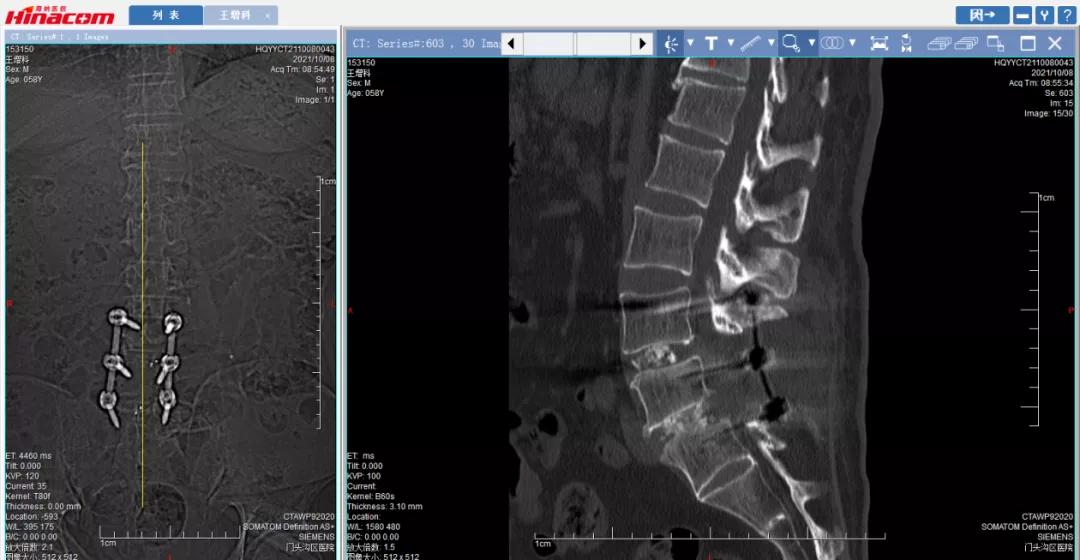

腰椎正位平片-术前

腰34椎间盘--术前CT

腰45椎间盘--术前CT